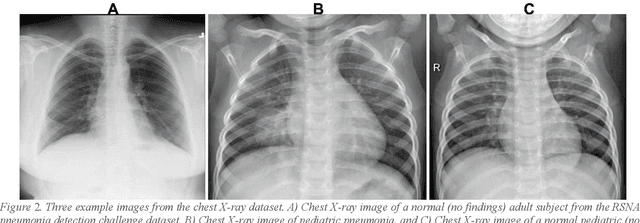

Abstract:Despite the great potential of machine learning, the lack of generalizability has hindered the widespread adoption of these technologies in routine clinical practice. We investigate three methodological pitfalls: (1) violation of independence assumption, (2) model evaluation with an inappropriate performance indicator, and (3) batch effect and how these pitfalls could affect the generalizability of machine learning models. We implement random forest and deep convolutional neural network models using several medical imaging datasets, including head and neck CT, lung CT, chest X-Ray, and histopathological images, to quantify and illustrate the effect of these pitfalls. We develop these models with and without the pitfall and compare the performance of the resulting models in terms of accuracy, precision, recall, and F1 score. Our results showed that violation of the independence assumption could substantially affect model generalizability. More specifically, (I) applying oversampling before splitting data into train, validation and test sets; (II) performing data augmentation before splitting data; (III) distributing data points for a subject across training, validation, and test sets; and (IV) applying feature selection before splitting data led to superficial boosts in model performance. We also observed that inappropriate performance indicators could lead to erroneous conclusions. Also, batch effect could lead to developing models that lack generalizability. The aforementioned methodological pitfalls lead to machine learning models with over-optimistic performance. These errors, if made, cannot be captured using internal model evaluation, and the inaccurate predictions made by the model may lead to wrong conclusions and interpretations. Therefore, avoiding these pitfalls is a necessary condition for developing generalizable models.

Abstract:Shortage of labeled data has been holding the surge of deep learning in healthcare back, as sample sizes are often small, patient information cannot be shared openly, and multi-center collaborative studies are a burden to set up. Distributed machine learning methods promise to mitigate these problems. We argue for a split learning based approach and apply this distributed learning method for the first time in the medical field to compare performance against (1) centrally hosted and (2) non collaborative configurations for a range of participants. Two medical deep learning tasks are used to compare split learning to conventional single and multi center approaches: a binary classification problem of a data set of 9000 fundus photos, and multi-label classification problem of a data set of 156,535 chest X-rays. The several distributed learning setups are compared for a range of 1-50 distributed participants. Performance of the split learning configuration remained constant for any number of clients compared to a single center study, showing a marked difference compared to the non collaborative configuration after 2 clients (p < 0.001) for both sets. Our results affirm the benefits of collaborative training of deep neural networks in health care. Our work proves the significant benefit of distributed learning in healthcare, and paves the way for future real-world implementations.